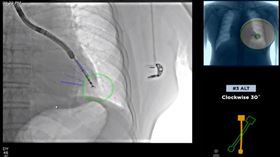

「零下40度微針」擊殺癌細胞 肺癌新救星

肺癌高居國內十大癌症致死率之首,每年有超過9千人死於...